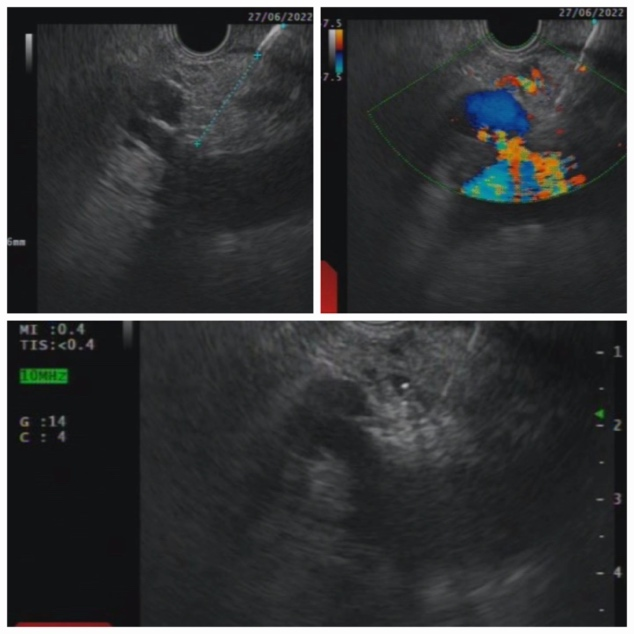

经过胥主任和家属的详细解释沟通、仔细评估陈阿姨的病情之后,胥主任决定给陈阿姨实施超声内镜下腹膜后神经节阻滞术(EUS-CPN),该技术是应用线阵超声内镜将药物注射于腹腔神经节区域,可以有效缓解胰腺癌引起的剧烈腹痛。在胥主任的精准施术下,陈阿姨不仅腹痛得到明显缓解,连平时使用的止痛药也减量了,目前已康复出院!

经超声内镜引导下的腹腔神经节阻滞术(EUS-CPN)手术过程

大家可能听说过:胰腺癌是“癌中之王”,晚期胰腺癌的疼痛令病人躯体、精神备受折磨,严重影响生活质量,有人因恐惧而产生自杀的念头。晚期胰腺癌疼痛很难控制,有时吗啡类药物也难以缓解疼痛,且此类药物有便秘、排尿不畅、恶心呕吐、嗜睡等副作用,甚至损害免疫系统。经超声内镜引导下的腹腔神经节阻滞术(EUS-CPN)的应用给患者带来了福音,该技术是应用线阵超声内镜将药物注射于腹腔神经节区域,可以有效缓解胰腺癌引起的剧烈腹痛。EUS-CPN 特别适于治疗晚期胰腺癌的腹痛,是晚期胰腺癌安全、高效、经济的镇痛方案。

超声内镜引导下的神经丛阻滞术操作时间平均15-20分钟,是一种内镜引导的微创手术,疗效确切。适应于确诊的恶性肿瘤,已无手术切除机会,疼痛症状明显,经非侵入性治疗(如口服阿片类药物)效果不佳者;顽固性腹痛的慢性胰腺炎患者也可行CPN。而一些凝血功能障碍;血小板减少症;有严重的腹腔感染 ;不能耐受超声内镜的终末期肿瘤;其他内镜检查禁忌证;以及一些如手术后解剖位置发生改变的不适宜穿刺的患者则不适宜此项操作技术。